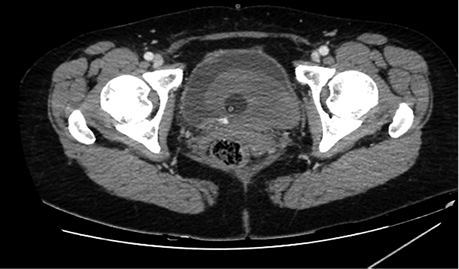

Figure 3. Blood in bladder (grey area in bladder), small amount of contrast in the bladder (bladder is full, with catheter inside it)

Pseudoaneurysm was embolized with two 8 mm x 20 cm coils, an additional coil of 12 mm x 30 cm (Figure 5).

Control angiography with contrast was performed. Pseudoaneurysm was completely occluded and no longer visible (Figure 6). No extravasation was found.

After embolization, creatinine decreased till 83 µmoL/L and eGFR was 73 mL/min/1.73 m2. Pseudo­aneurysm was no longer visible, as well as small segmental branches. Vascularization of renal parenchyma is reduced.